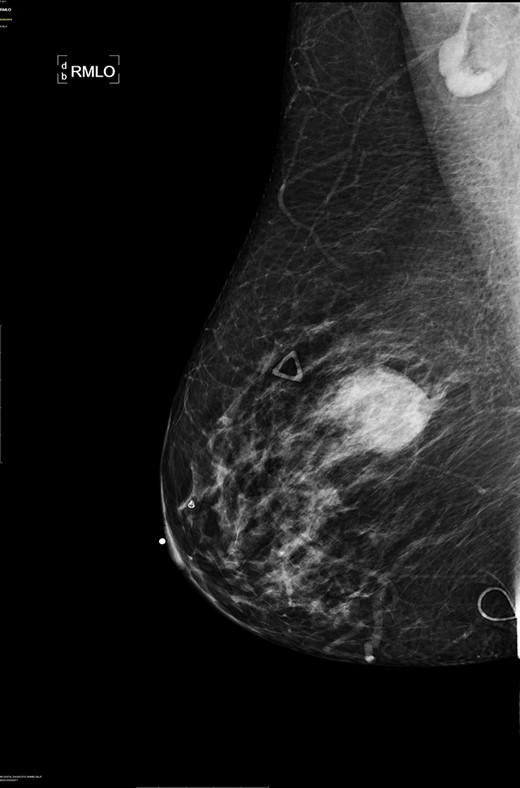

A diagnostic mammogram and ultrasound were performed to evaluate the right breast mass. The right breast imaging was categorized as BIRADS 5 (Figs 1–3). The patient underwent a right breast ultrasound-guided vacuum core biopsy of the mass and a fine needle aspiration (FNA) of the enlarged lymph node in the right axilla. Pathology of the core biopsy revealed poorly differentiated squamous cell carcinoma with tumor necrosis and calcification (Figs 4 and 5). Cytology of the right axillary lymph node was negative for metastatic carcinoma.

Right breast cranio-caudal and mediolateral oblique mammographic views, demonstrate a smooth, well rounded, mammographic density, corresponding to the palpable right breast mass. In addition, a prominent right axillary lymph node is noted in the mediolateral oblique view.